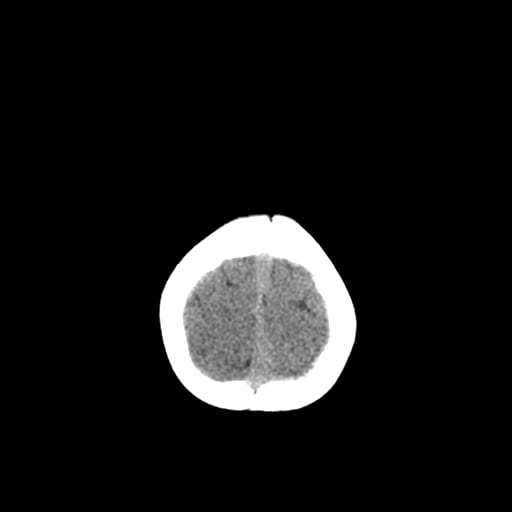

Age: 1

Sex: Male

Indication: Fall